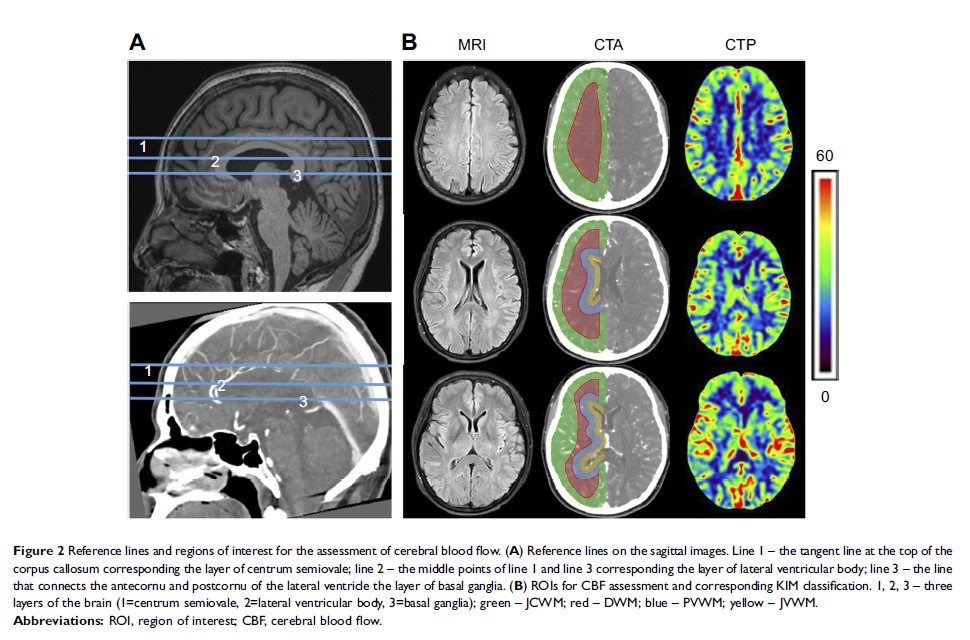

阿尔茨海默氏病患者脑灌注与白质病变 KIM 评分的相关性分析